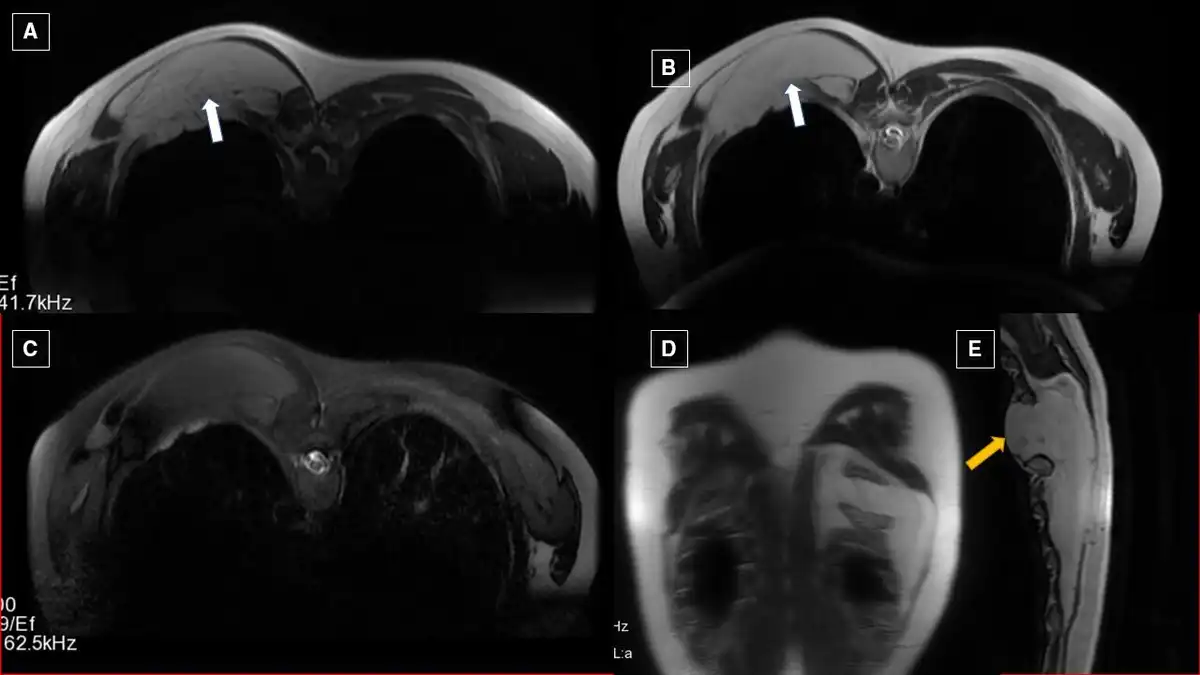

Plain radiograph of the right chest revealed normal study. MRI of the left scapula revealed a hyperintense lesion (12×1.7×12 cm) on the left paravertebral region extending from D5 to D12, which is suppressed on STIR sequence (figure 1). The lesion was also extending into the fifth intervening intercostal space, causing its widening due to mass effect. Visualised vertebral bodies showed normal signal intensity and morphology. The final impression of MRI was lipoma. Tru-cut biopsy was performed which was suggestive of lipoma.

Axial T1WI (A) and T2WI (B) showing hyperintense lesion (marked by white arrow) in the left paravertebral region extending from D5 to D12 levels, which is suppressed on fat suppressed sequence, that is, stir (C). Corresponding coronal (D) and sagittal (E) T2WI showing the extent of the lesion. Protrusion of lipoma causing intercostal widening is marked by yellow arrow (WI—weighted image, STIR—short τ inversion recovery sequence).